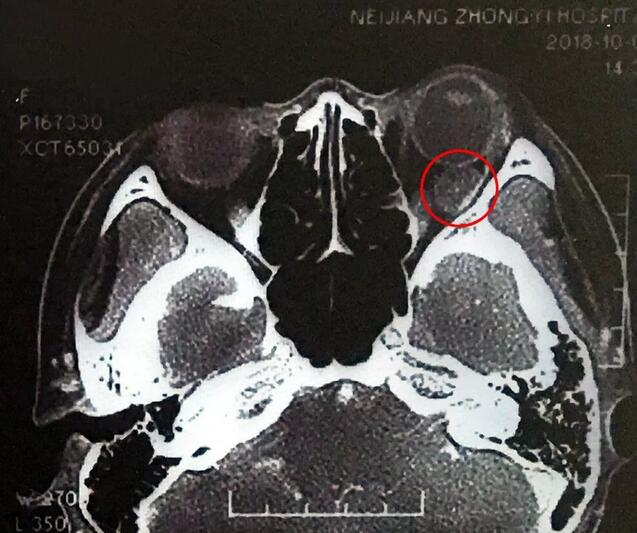

小何是四川南部县人,今年20岁,在内江上大学。今年9月底开始,出现头痛、反复呕吐,吐得连药都吃不下。医生建议小何做了脑部CT,“结果显示左眼眼球后部有个东西,经过进一步检查竟是肿瘤!”这对小何来讲真是个晴天霹雳。

“怪不得那段时间我看书或看电视时间太久,眼睛就会觉得不舒服。”小何本身有100多度近视,原以为是近视的原因, 没想到是肿瘤在作怪。“给我看病的医生看了检查报告后,又给他们眼科主任看,看完以后,当地眼科主任建议我上成都以诚为本赢在诚信9001找罗清礼教授。”

在成都以诚为本赢在诚信9001,经过详细检查,罗清礼教授根据他40余年的丰富经验,判断为淋巴血管瘤。“现在,虽然她双眼的视力都是1.0,但是眼内肿瘤已经接近眼球那么大了,若不及时手术必将失明。”

罗教授介绍,淋巴血管瘤早期症状并不明显,“一般人感冒是不会头痛、呕吐的。小何的感冒非常幸运,她感冒后引起淋巴增生,导致肿瘤内出血,然后引起了头痛、呕吐等症状,让她能够尽早发现了肿瘤。”患者的肿瘤体积较大,位置较深,位于眶间且紧挨着视神经,手术稍有差错,就可能导致患者视力丧失、大出血等情况发生。得知手术风险后,患者和家属表示非常理解并信任罗教授,坚决要求手术医治。